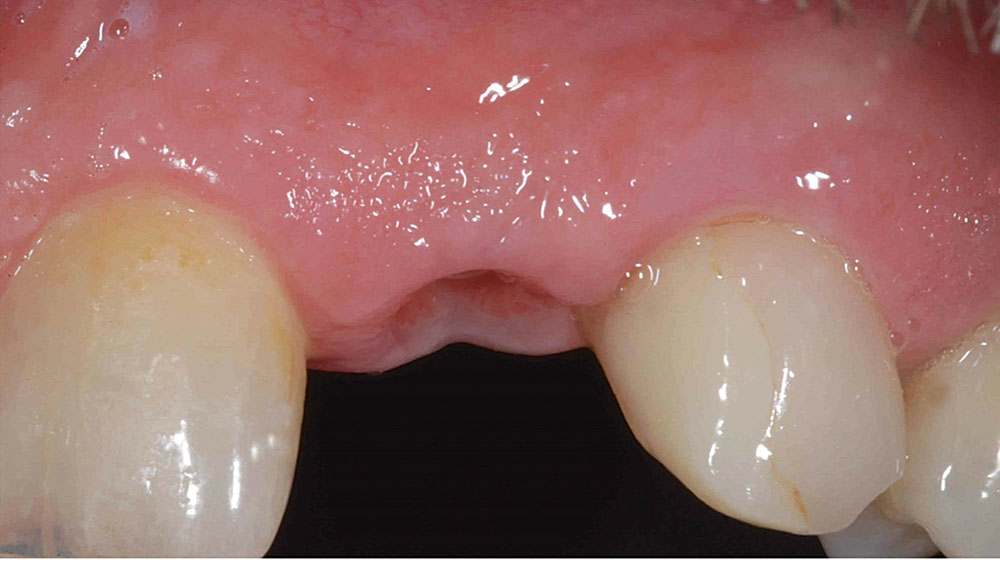

For the first few anterior cases, you should select clinical situations in which an untreatable tooth is removed, the extraction site is grafted, and the implant is placed after several months of healing. This approach allows you to develop the ideal soft-tissue contours and bone volume needed for straightforward implant surgery and a predictable outcome. Until you have more experience, I would not suggest extraction with immediate implant placement — unless you have Dr. Jack Hahn standing by your side! It’s also important to select patients who have favorable teeth alignment as well as a thick tissue biotype, both of which make it easier to achieve a natural emergence profile and esthetic result. High smile lines should be avoided.

Most patients desire an esthetic result when viewed with a mirror at a 10-inch distance. Placing an implant in a grafted, healed extraction site typically allows for the natural tissue tone and texture patients desire, as well as the keratinized soft tissue needed to fill the embrasures and avoid black triangles around the restoration. Achieving proper apicocoronal implant positioning as described above helps avoid any visible metal at the gum line. It’s also important to choose a ceramic material that blends well with the color, contours and texture of adjacent teeth.

This case is an example of an ideal clinical situation for dentists who are new to placing implants in the esthetic zone. The patient requested treatment for a fractured upper lateral incisor. After extraction, grafting and healing, ample bone and soft tissue were present, and an implant was placed in optimal position for an esthetic result. The screw-retained restoration predictably restored form and function, illustrating the beautiful results that can be achieved by observing simple surgical and prosthetic guidelines.